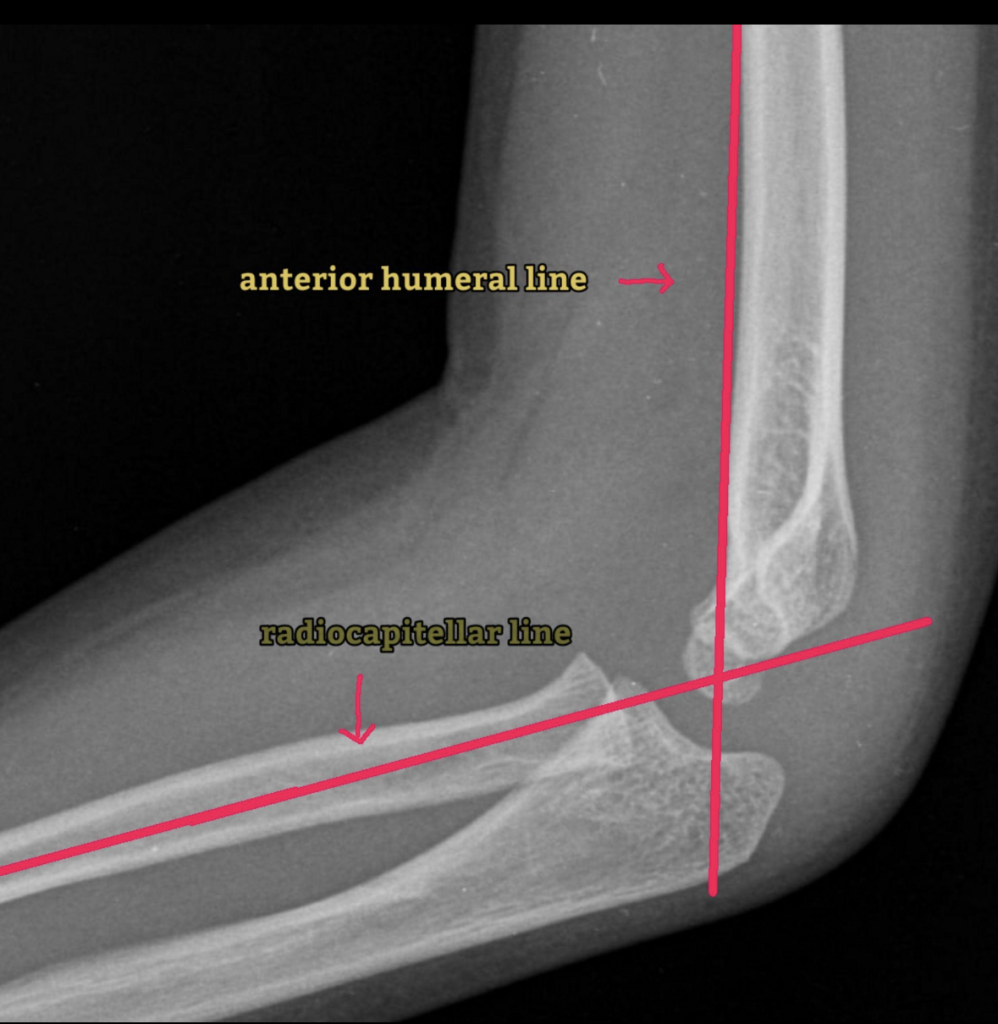

Radiocapitellar line, dirsek grafilerinde (özellikle çocuklarda) radius başı ile kapitellum hizasını değerlendirmek için kullanılan temel bir radyolojik referans çizgisidir.